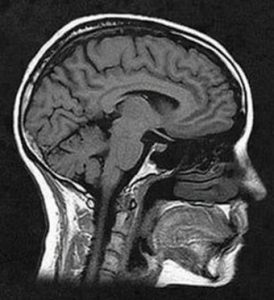

| MRI

|

Magnetic resonance imaging (MRI) produces “slices” that represent the human body through the application of magnetic signals. It lasts longer than a CT and is more detailed | – High- and – Very-high-field

-Low-to-mid-field – Ultra-high-field |

– Cardiology

– Vascular – Musculoskeletal – Neurology - Mom |